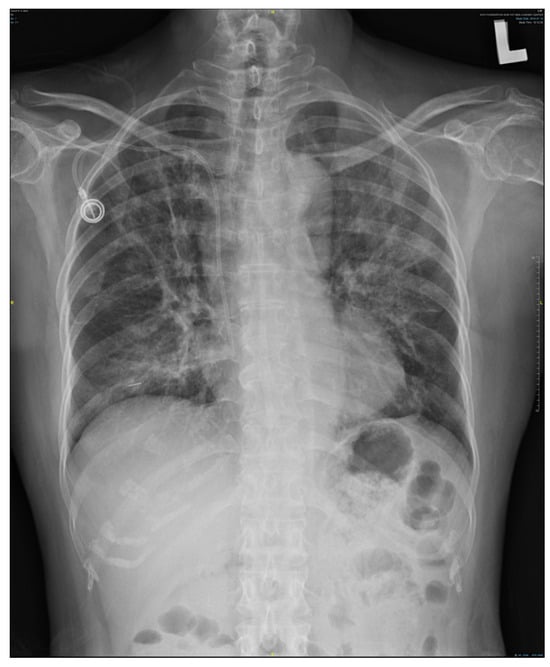

Figure 1.

Chest X-ray showing marked pneumonitis patches, demonstrating increasing bilateral lung infiltration.